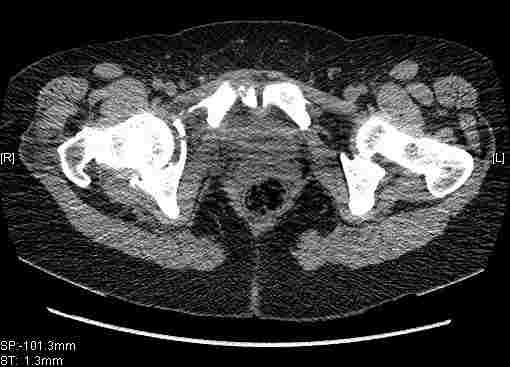

Удалось сегодня вывести пациентку в соседнюю больницу, где есть кт. Срезы сделаны только горизонтальные.

Следом 3d

Приветствую,Антон.Рункова рядом нет,но после полученных данных КТ,обсуждали совместно.Итог обсуждения-развернутый ответ дать не получится,т.к.срезы выбраны не информативные.Если ориентироваться на данные 3D,то ,ИМХО,можно лечить на вытяжении.